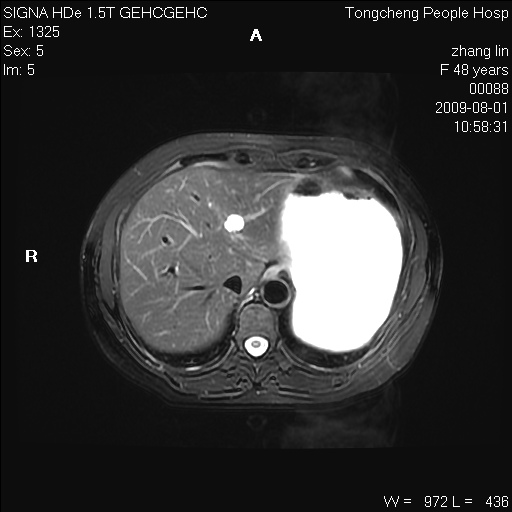

女,48岁。健康体检,彩超发现右肾占位性病变。平素健康。

临床诊断:右肾占位性病变,性质待定(囊肿?肿瘤?)。

上中腹部mr平扫+增强扫描,图像如下:

右肾上极见一类圆形病灶,t1wi呈等信号t2wi呈等高混杂信号,三期增强无强化,边界清---考虑囊肿出血。

同反相位均表现为等信号,病变无强化,考虑含蛋白的囊肿可能,弥散加权相或许有些帮助,

肝囊肿